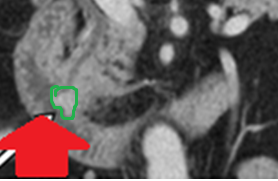

CT — Well-circumscribed nodule in contact with the lower pole of the left thyroid lobe (Courtesy Dr. V. Penopoulos)